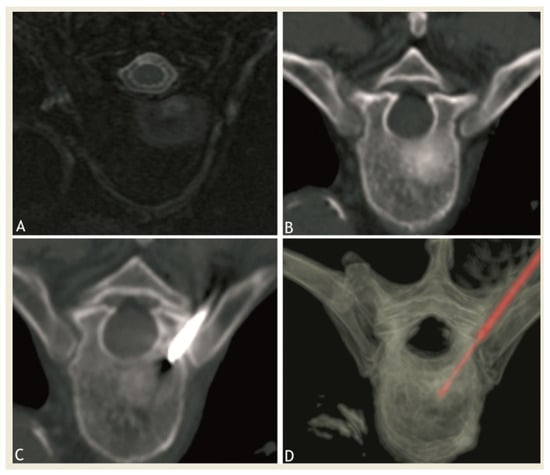

2.2. RFA Technique